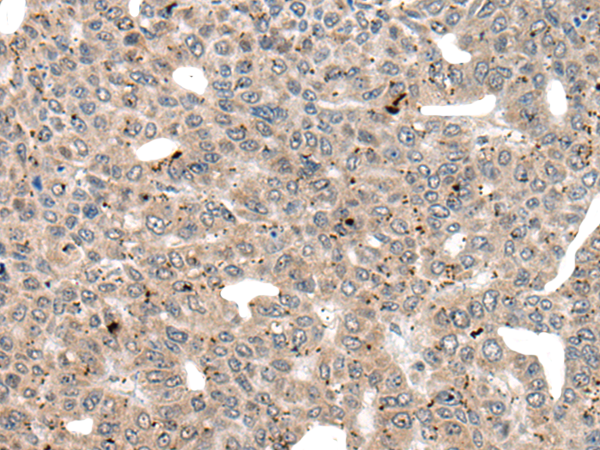

分类: 科研抗体货号: P06279别名:应用: WB,IHC反应种属: Human, Mouse, Rat